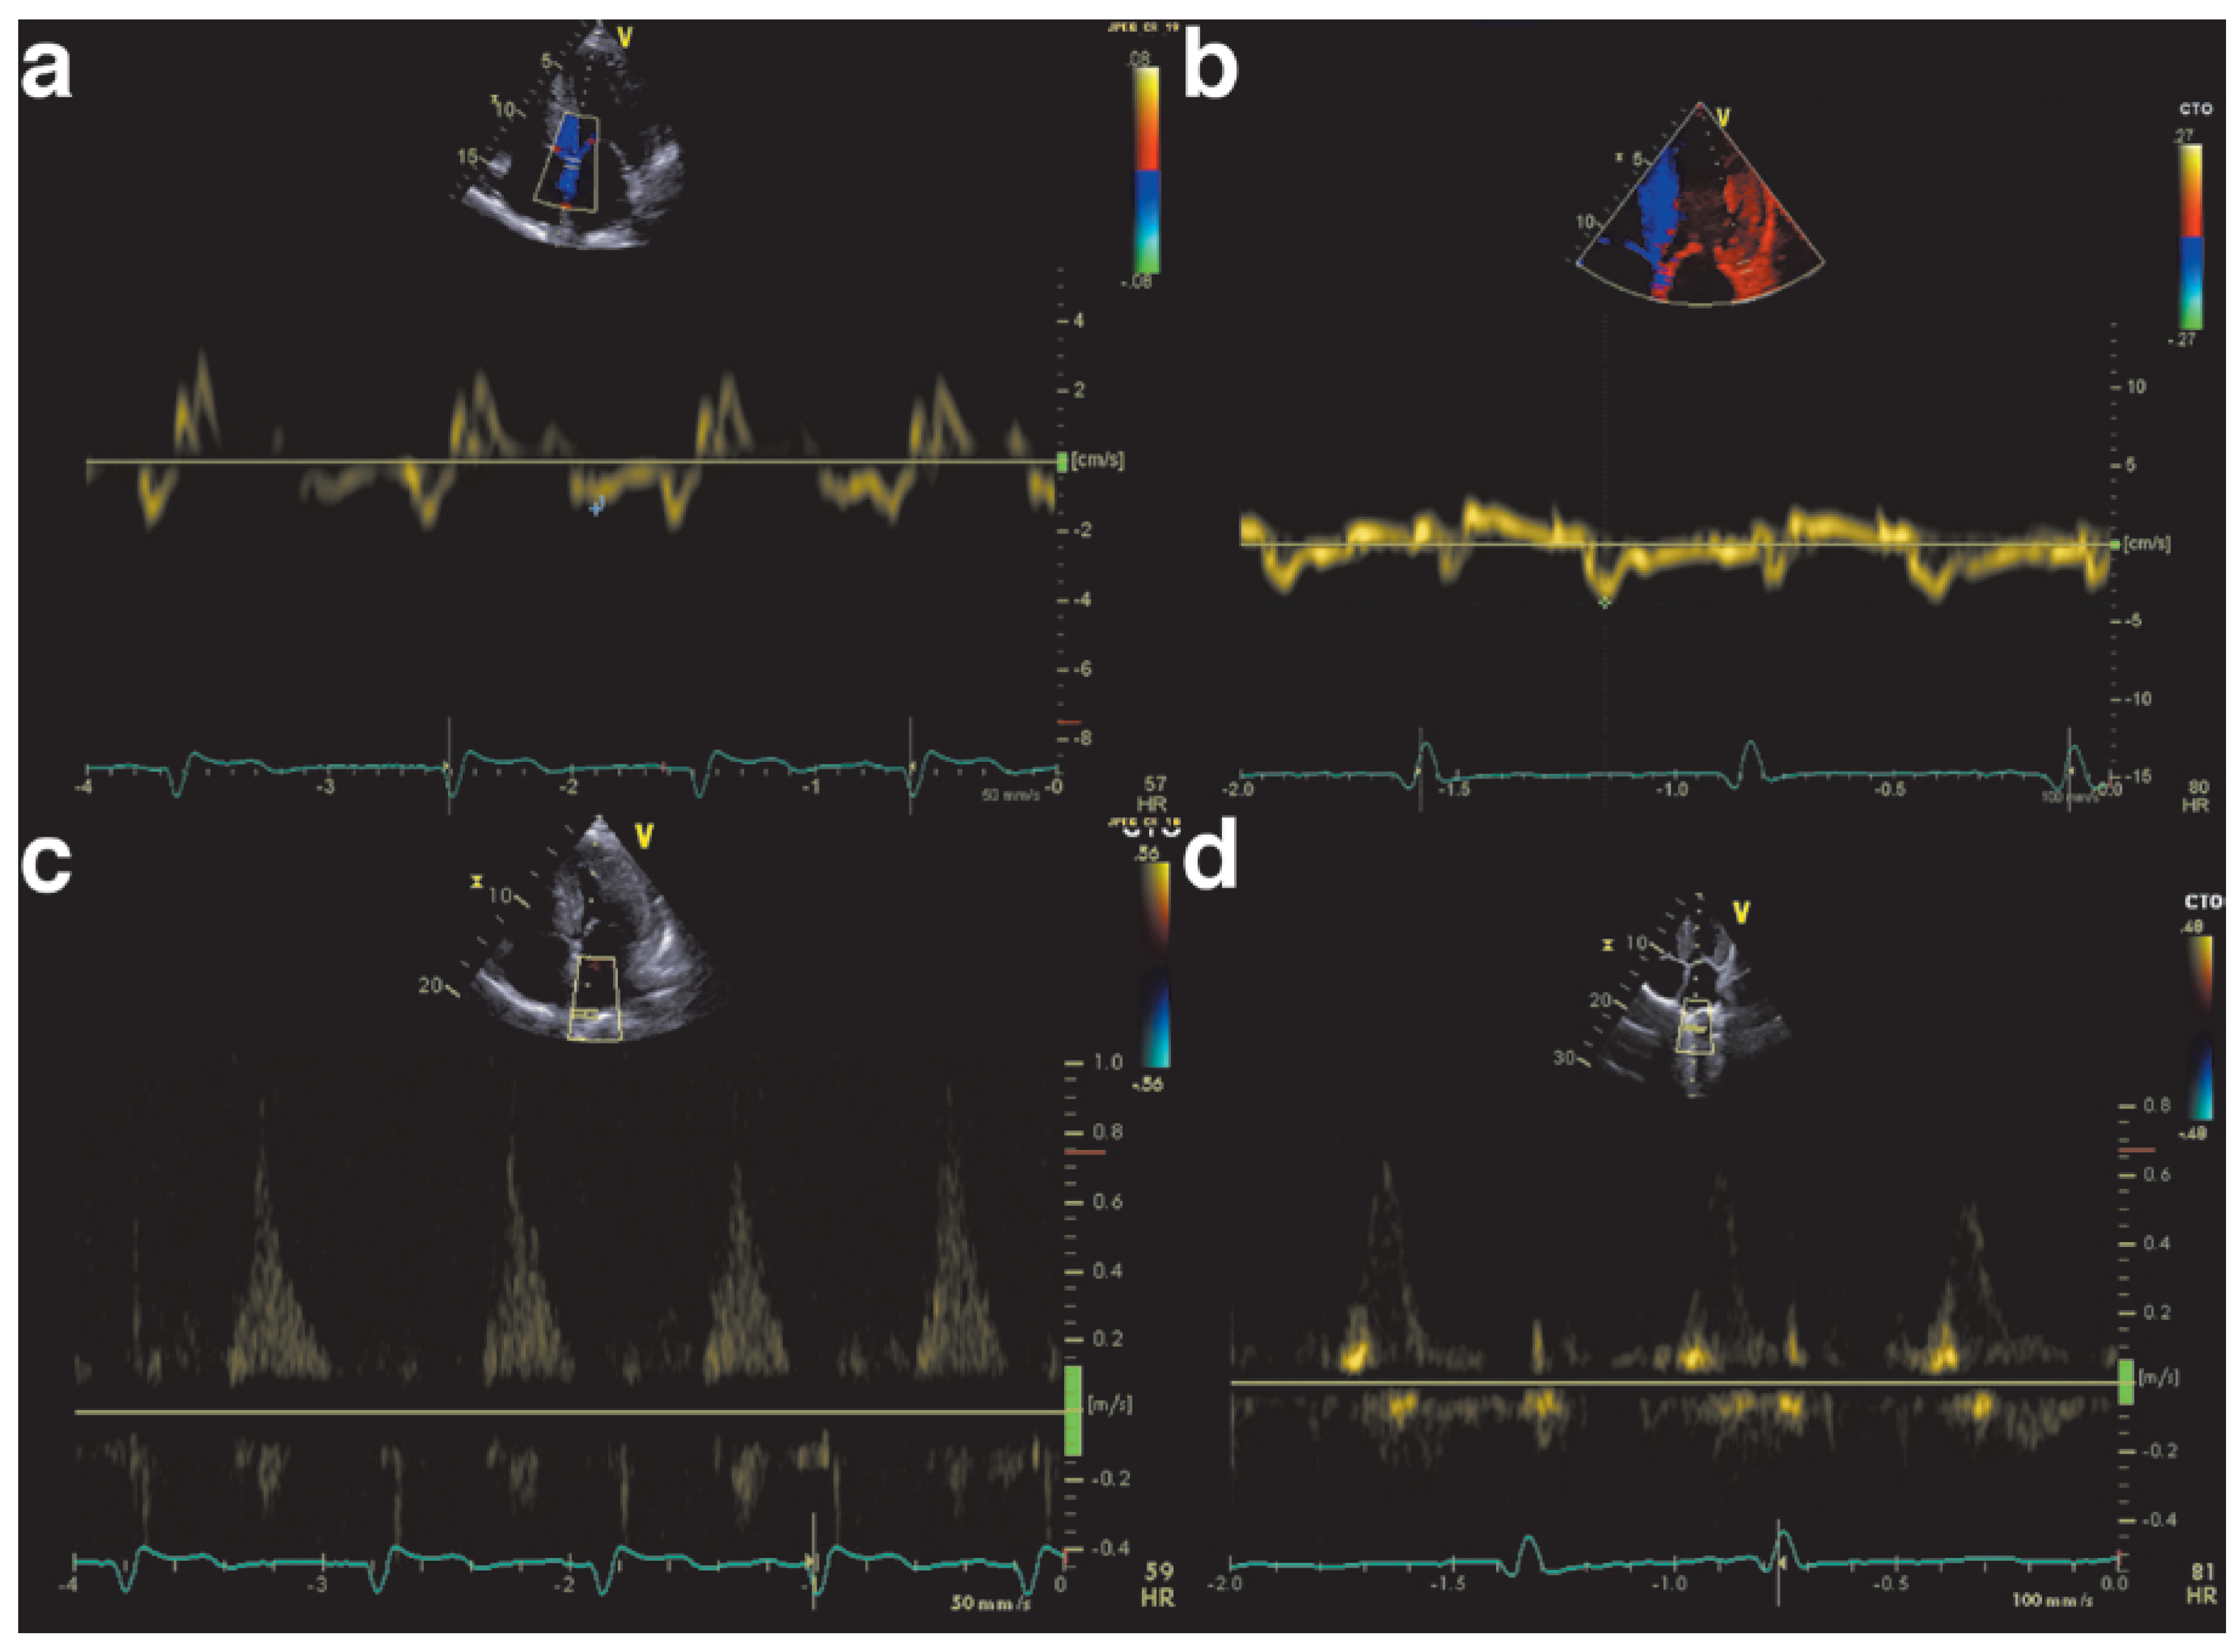

Echocardiography is key in detecting cardiac involvement in amyloidosis. Ohen, a hypertrophic cardiomyopathy is initially suspected on the basis of increased wall thickness and low ventricular volume (Figure 2). Tissue Doppler and strain measurements are especially important to detect diastolic and systolic dysfunction as patients initially present with HFpEF. The ventricle will first show diastolic dysfunction (Figure 3) due to noncom-pliance of the infiltrated myocardium, and in more advanced stages systolic dysfunction. Cardiac amyloidosis is characterised by regional variations in longitudinal strain, typically with apical sparing (Figure 4). Also a “granular sparkling appearance” of the leh ventricle is typical (important: switch off second harmonic imaging, as it may produce sparkling appearance in non-amyloidosis patients). Doppler measurements show restrictive filling patterns with increased leh ventricular filling pressures. Additionally the aortic and mitral valves appear thickened (amyloid deposits), as well as the intra-atrial septum and the right ventricle. The atria are typically dilated and quite ohen a pericardial effusion is found. The combination of echocardiographic signs of hypertrophic cardiomyopathy and a normal or low voltage ECG have a high sensitivity and specificity for amyloidosis [9,10,11].

Figure 3. Echocardiographic example of diastolic dysfunction in amyloidosis. Panels a and b show low septal and lateral tissue Doppler e’ values, characteristic of high left ventricular end diastolic pressure. Panels c and d show decreased pulmonary vein systolic flow, and increased diastolic flow.